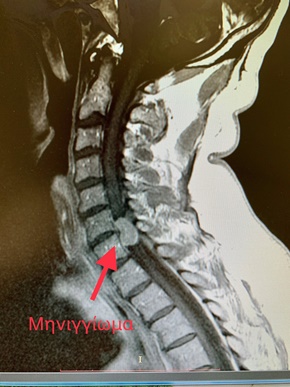

Αφαίρεση Όγκου Σπονδυλικής Στήλης (Δίλοβο Μηνιγγίωμα Μεγέθους 2εκ.)

Ασθενής 58 ετών με διαταραχές αισθητικότητας και κινητικότητας μέχρι το επίπεδο Α6 νευροτομίου (επίπεδο του Α6, Α7 σπονδύλου) λόγω όγκου (μηνιγγιώματος) στην αυχενική μοίρα της σπονδυλικής στήλης, υπεβλήθη σε νευροχειρουργική επέμβαση για την αφαίρεσή του.